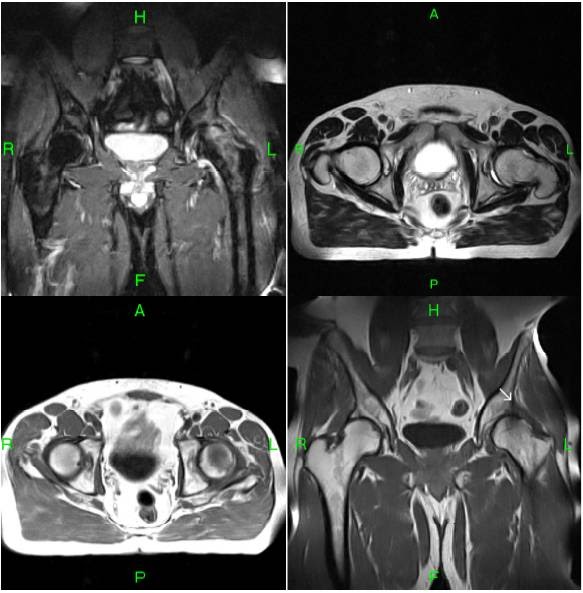

MRI HIP CAM FAI FEMORO ACETABULAR IMPINGEMENT Radedasia Cam Type Fai Mri Pelvic radiography with dedicated hip projections is the basis of the diagnostic workup of patients with suspected fai to assess arthritic changes and acetabular. Similar to ct mri allows the assessment of cam and/or pincer morphology. Mri provides a useful assessment of patients in whom a femoroacetabular impingement is clinically suspected. Pincer, cam, and mixed [ 2 , 3 ].. Cam Type Fai Mri.